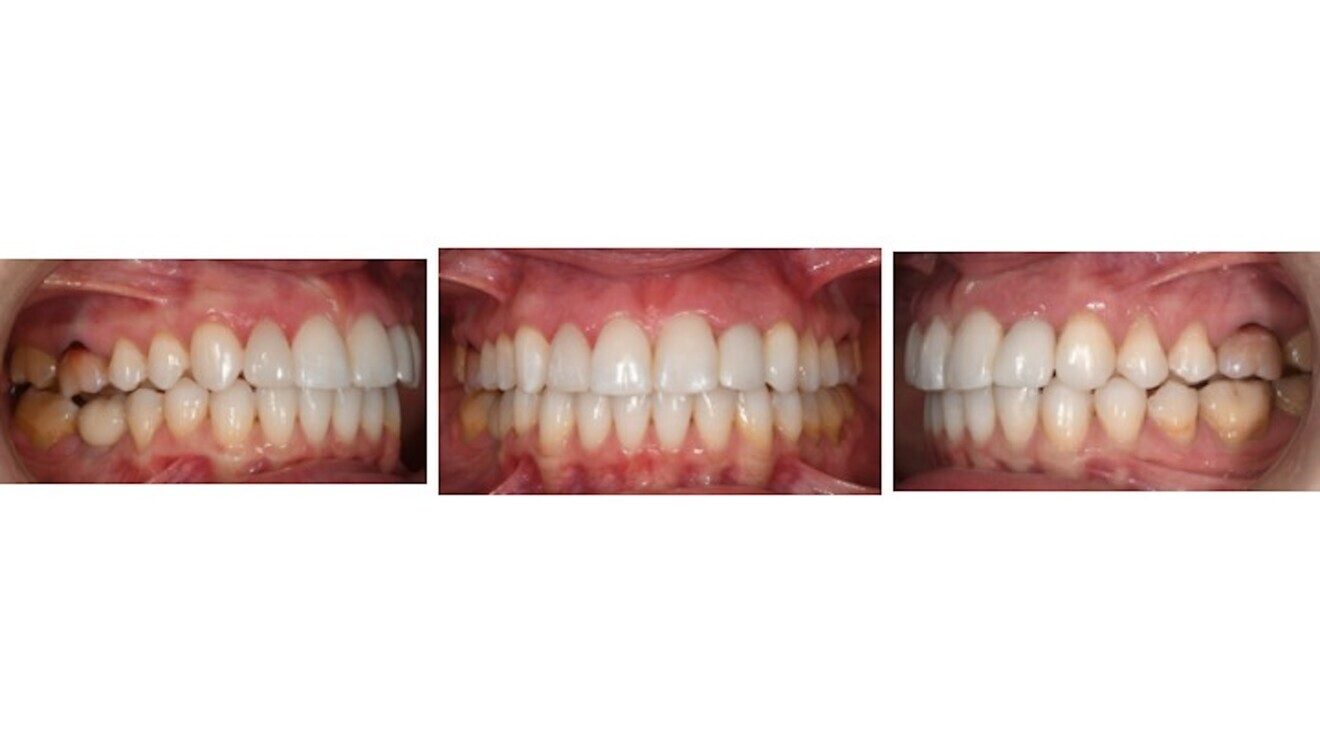

Figs. 10a–c: Lateral and frontal intra-oral photographs after orthodontic treatment and implant placement. Tooth #12 had not yet been prosthetically restored.

The panoramic radiograph after orthodontic treatment showed the correct parallelism in the maxillary left anterior region for the implant placement and the convergence of the roots of teeth #44 and 45 (Fig. 9), but we decided not to spend extra treatment time on the latter, since the patient was really pleased with the result at that point. After completion of orthodontic treatment, perfect Class I molar and canine relationships had been achieved and the midlines were coincident. A temporary crown was placed on the single implant (Figs. 10 & 11), and prosthetic restoration of tooth #12 and final restoration of the implant were completed. An excellent final result was achieved. The soft tissue in the implant area had completely healed, contributing to the high-level aesthetics achieved (Figs. 12–15).